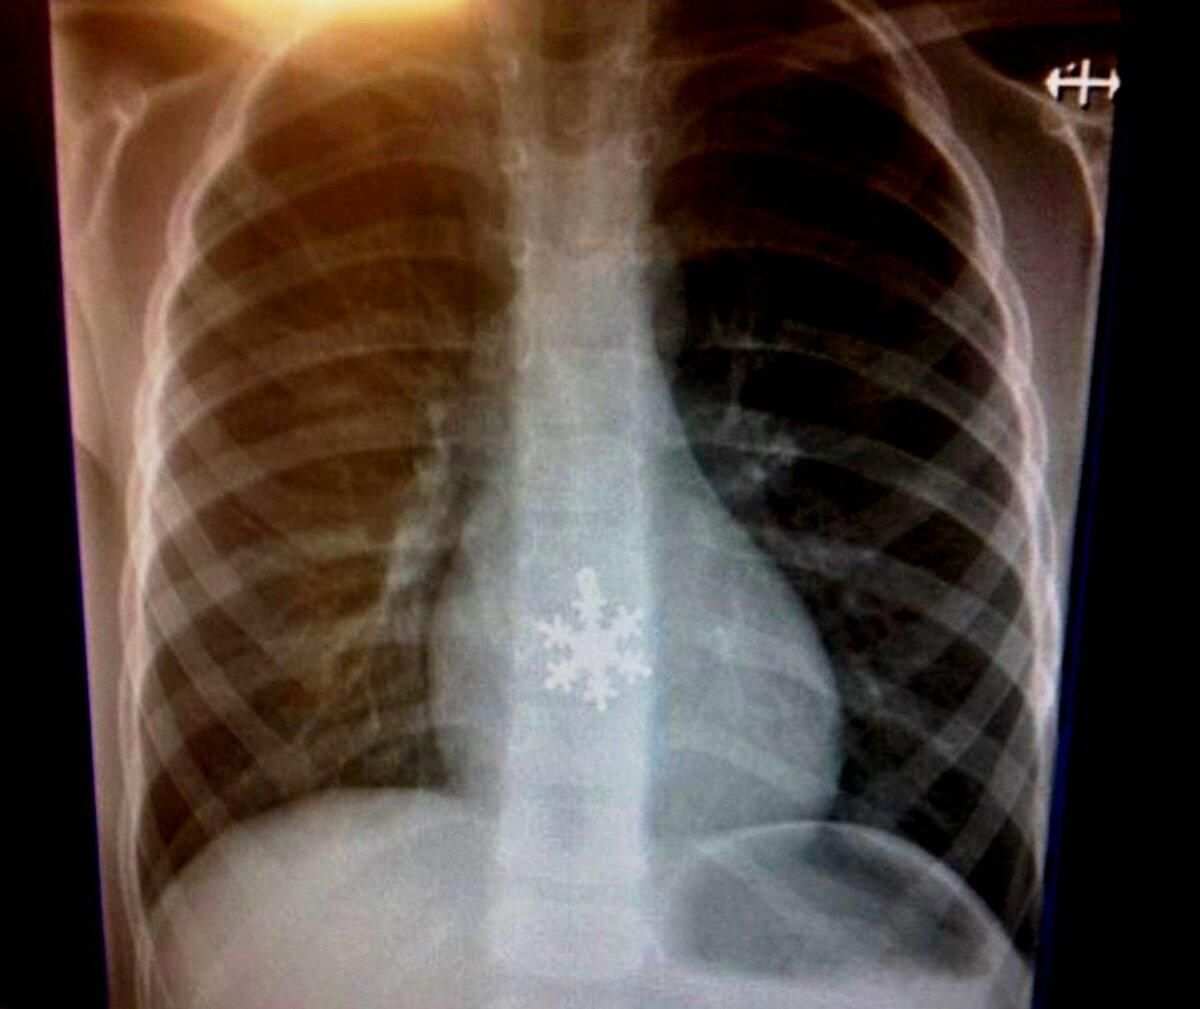

Ничего особенного. Просто кто-то проглотил… снежинку

Фото onedio